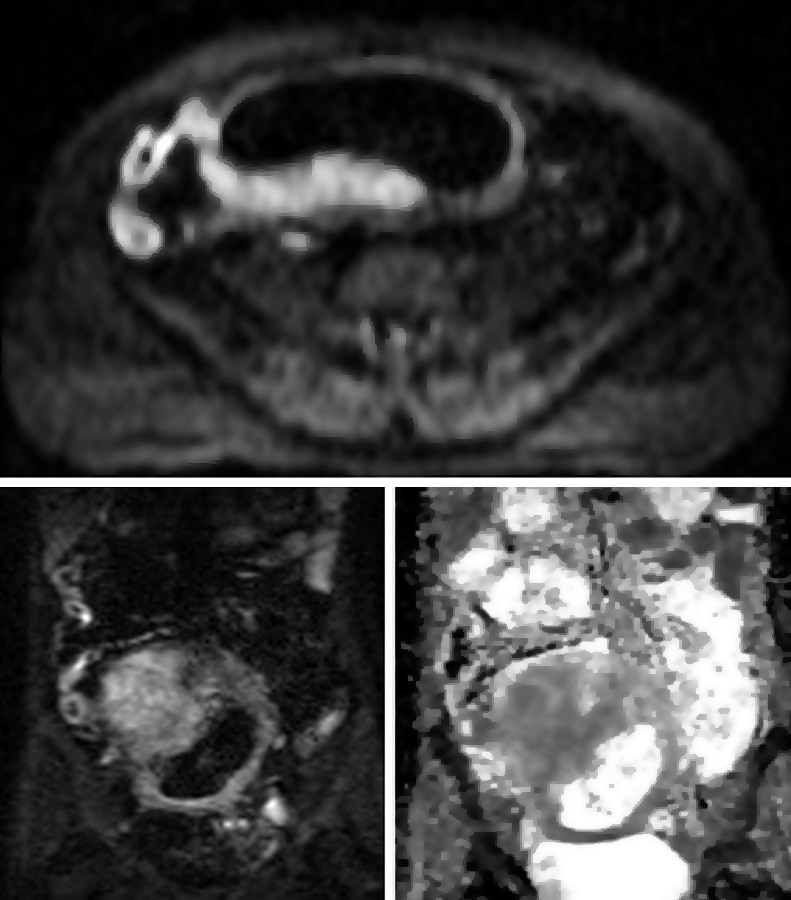

Figura 2

Paciente de sexo masculino de 9 años con antecedente de resección colónica y ostomía por enfermedad de Crohn. a) Secuencia eco de gradiente coronal donde se idenjpgica el engrosamiento parietal del asa detransitada de 6 mm de espesor (punta de flecha).

b) Misma secuencia muestra adenomegalias ileocólicas de hasta 10 mm como elemento de actividad (punta de flecha).

c) Secuencia T2 axial con saturación grasa evidencia edema submucoso como una banda hiperintensa central entre la mucosa y serosa (flecha).